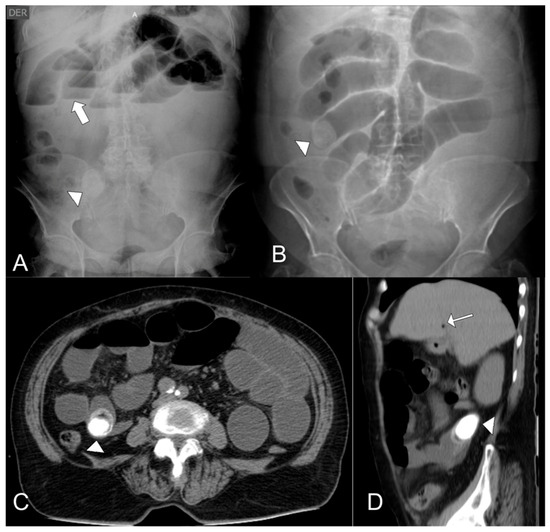

A total of four patients are presented in this case series. All the patients were in their eighth decade of their life and 75% were female. Regarding symptoms, all patients presented vomit and abdominal pain, however only one presented signs of acute abdomen. Vital signs only reported one patient with tachycardia and two with high blood pressure. Preoperative hemogram reported leukocytosis and neutrophilia in every patient, a high level of creatinine of one patient, and high glycemic levels in one patient. CT scans reported gallstones inside the intestinal tract (Figure 1) and cholecystoduodenal fistula (Figure 2) as findings. Every patient had an enterotomy as a surgical procedure. However, two patients had also a subtotal cholecystectomy. Surgical procedures also evidenced the presence of gallstones which were documented via photographs and removed (Figure 3). Evaluating complications, one patient had a surgical site infection, while the other was diagnosed with healthcare-related pneumonia. The other two patients did not present any complications. The average hospital stay was 9.5 days. One patient required treatment in the ICU (Table 1).

Figure 1.

(A) Plain abdominal X-ray showing a radiopaque object in the right flank (arrowhead), consistent with a gallstone, along with stepladder-pattern air-fluid levels (thick arrow). (B). Scout view from an abdominal computed tomography (CT) scan demonstrating a gallstone in the right flank (arrowhead) and dilated small bowel loops. (C). Axial contrast-enhanced abdominal CT scan revealing a thick-walled gallbladder containing a large calculus, along with pneumobilia and passage of oral contrast into the gallbladder. (D). Coronal contrast-enhanced abdominal CT scan showing a gallstone at the jejunal level (arrowhead) with a second, smaller adjacent gallstone, as well as pneumobilia (arrow).